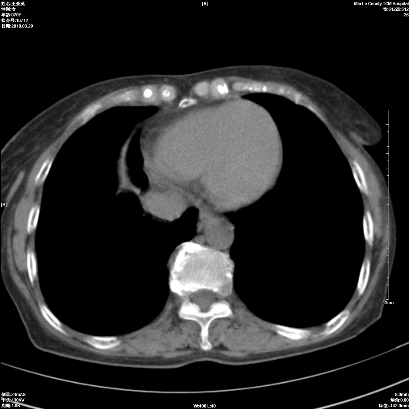

标题: CT25424:女性,70岁,胸闷、咳嗽月余。 [打印本页]

标题: CT25424:女性,70岁,胸闷、咳嗽月余。

1、右侧中央型肺癌伴右肺上叶不张建议支气管镜检   2、右肺中叶及下叶陈旧性病灶   3、肝内多发低密度影,肝内多发转移不除外,建议ct增强!

肝脏多发占位建议增强检查

1)考虑右肺中央型肺癌伴右肺上叶肺不张,右肺门淋巴结转移;建议行支纤维镜检查。2)右肺中叶、下叶及左肺上叶舌段感染性病变。3)肝内多发低密度影,不排除转移瘤可能;建议行ct增强扫描检查。

ct所见:右肺上叶肺不张,呈软组织密度影向肺门区聚拢,其内可见含气段支气管及细支气管影,病灶内尚可见钙化结节。右肺上叶支气管狭窄,段支气管壁可见钙化。右肺下叶背段、右肺中叶见不规则小片絮状影及纤维条索影,形态较僵硬。右肺中叶胸膜旁可见多个小结节影。纵膈内见钙化淋巴结。

分析:右侧胸廓及右肺体积缩小,说明病变时间比较长了,应该是有数年的时间了,如果是短期内出现的肺不张,只会引起纵膈向患侧移位,而不会引起胸廓的塌陷。不张的肺组织内可见含气支气管影,说明右肺上叶支气管没有完全中断,只是狭窄。右肺中叶、下叶散在不规则病灶,部分呈纤维化改变。纵膈内的淋巴结大部分钙化。因此,本例给我的感觉良性病变的可能是大。

结论:考虑右肺上叶支气管内膜结核合并右肺上叶肺不张;右肺中叶、下叶陈旧性肺结核改变。